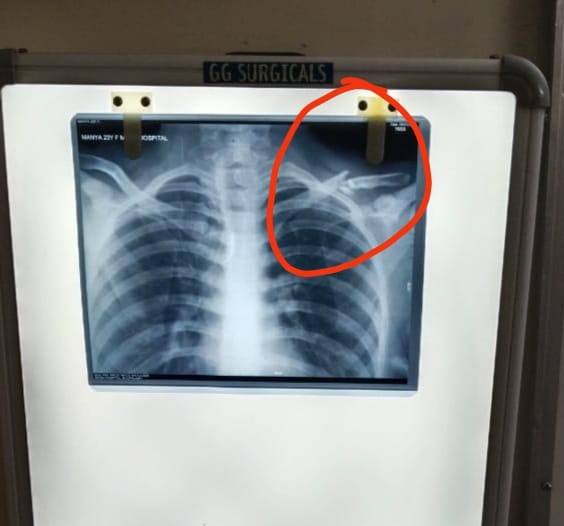

Hi Doctor, my 26 year old sister fallen from scooty and her clavicle bone broken, please find attached x-ray and please advise if surgery necessary or it can fix with belt only

What could be the best option for clavicle bone fracture

What will be best treatment for if clavicle bone broken